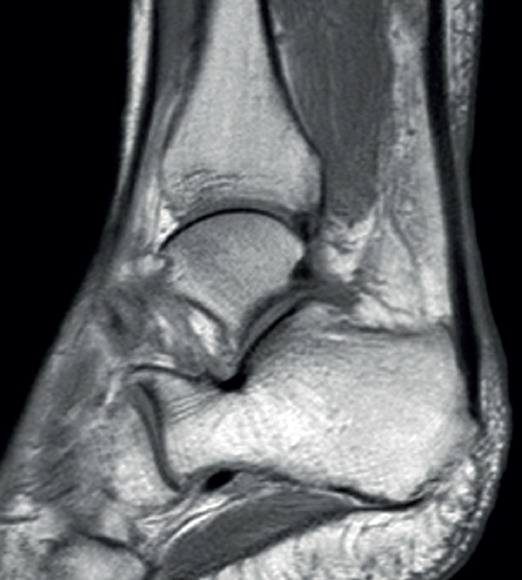

Figure 4. Sagittal magnetic resonance imaging view showing subacute non-insertional Achilles tendon rupture. Hyperintensity area between the two extremities.

Lastly, in acute Achilles tendon rupture, MRI shows the hematoma and also herniation of Kager's fat pad - these signs being similar to those identified by ultrasound (Figure 4). In chronic ruptures, MRI is the best diagnostic tool. Loss of continuity between the extremities is observed in T1 sequencing, while T2 imaging evidences hyperintensity between the two tendinous extremities due to the interpositioning of connective tissue and cicatricial changes(36).